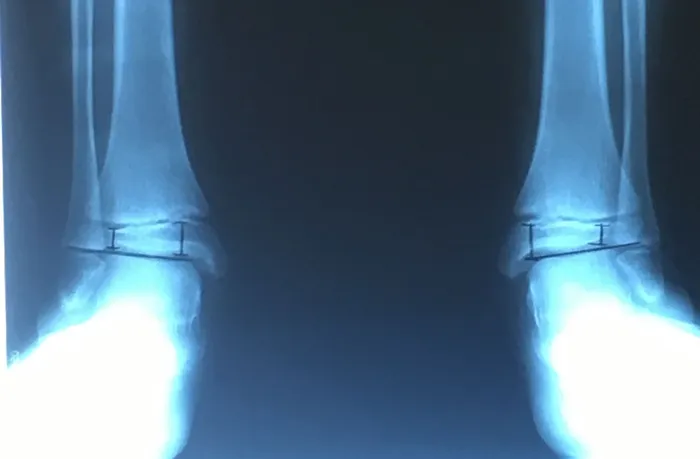

Pre and Postop Subtalar Implant and Percutaneous Achilles Lengthening Below. The first pics show wedging of the distal tibia physis causing ankle valgus due to constant pressure caused by the severity of the flatfoot (JT)